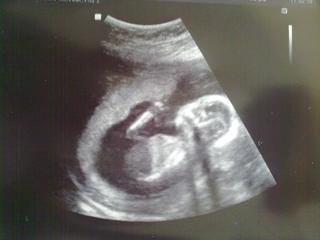

Tak se mi podarilo prihodit nejaky fotky (hura, mam superfoto moulusmoulu 🙂)

ahojky holky tak se hlásíme z další poradny 🙂 sme v 16tt a mimi se činí 😀 krev na tripli máme zasebou ted jen čekat za 10dní na výsledky (mám si prý zavolat) Jinak kvůli dovoléne pana doktora jdeme za 3 týdny na velký ultrazvuk tak se moc těším. Mimíšek dneska v bříšku se předváděl( jak kdyby tancoval) 😀 ty jeho mini nožičky a mini ručičky jsou božské. Jo taky jsem se zeptala na pohlaví 😀 mimi byl natočenej tak že skoro nic nešlo vidět ,ale pan doktor prohodil "vidím tam nějakej camfrnous " 😀 tak asi mimi holčička nebude .. uvidíme za 3 týdny to už mi řekne určo 🙂 pohladte bříška a krásný den 🙂